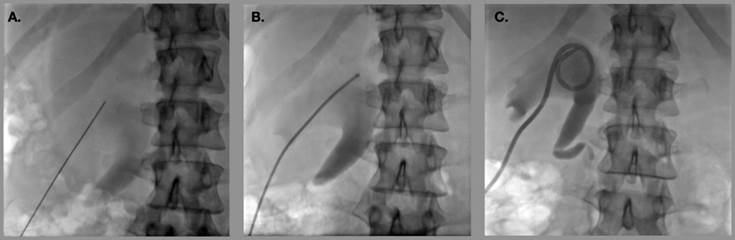

Independientemente del catéter empleado, todos requieren acceso renal y la técnica para colocación de nefrostomía guiado por imagen es la misma (Figura 1).

Se avanza aguja tipo Chiba o punta diamante a cálices mayores del polo inferior renal bajo guía sonográfica (A). Posteriormente se realiza recambio por sistema Neff y se opacifica el sistema colector (B). Finalmente se realiza recambio por catéter de nefrostomía (C).

Figura 1 Colocación de nefrostomía